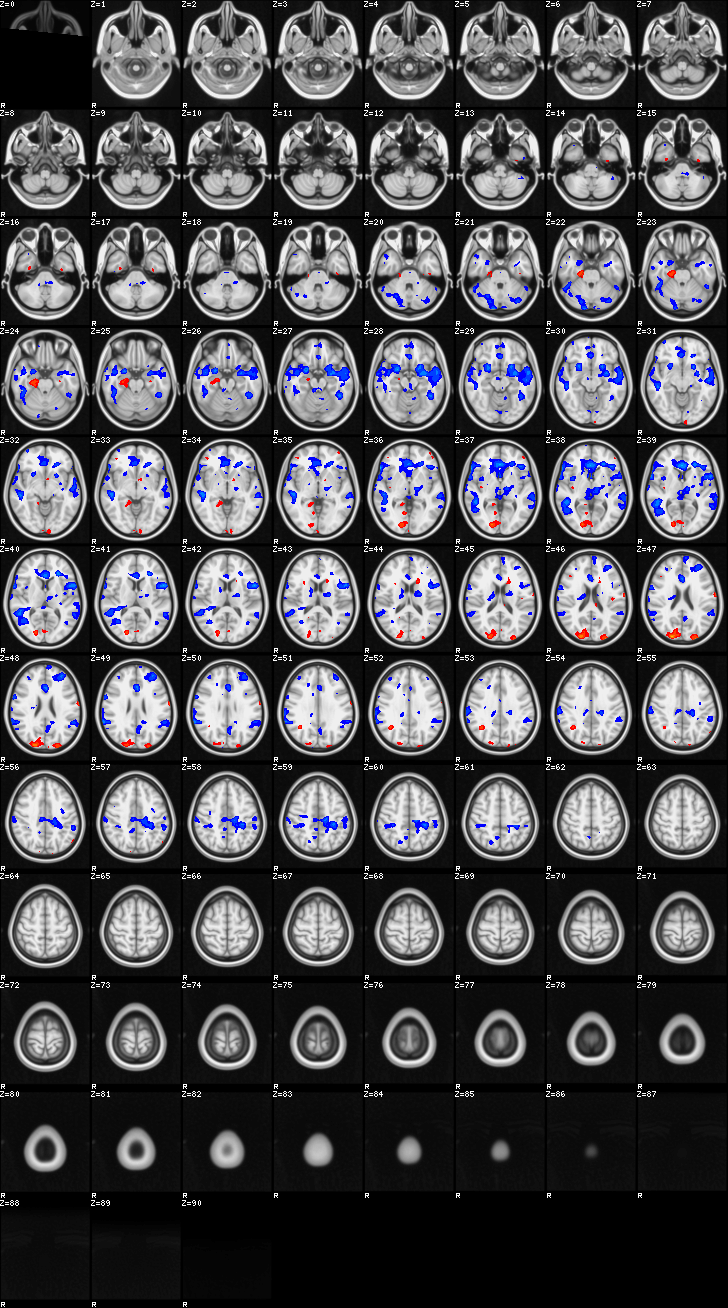

Fixed Effect¶

ATM it is 8 subjects, 8 mm FWHM spatial smoothing, preliminary results only

Images thresholded abs value > 2.3 and colormap goes from 2.3 to 5 (red->yellow) or -2.3 to -5 (blue->lightblue)

Contrasts:

- FltC

- Well – the opposite, and since both sides are plotted, it is just inverted colormap

01-FltC¶